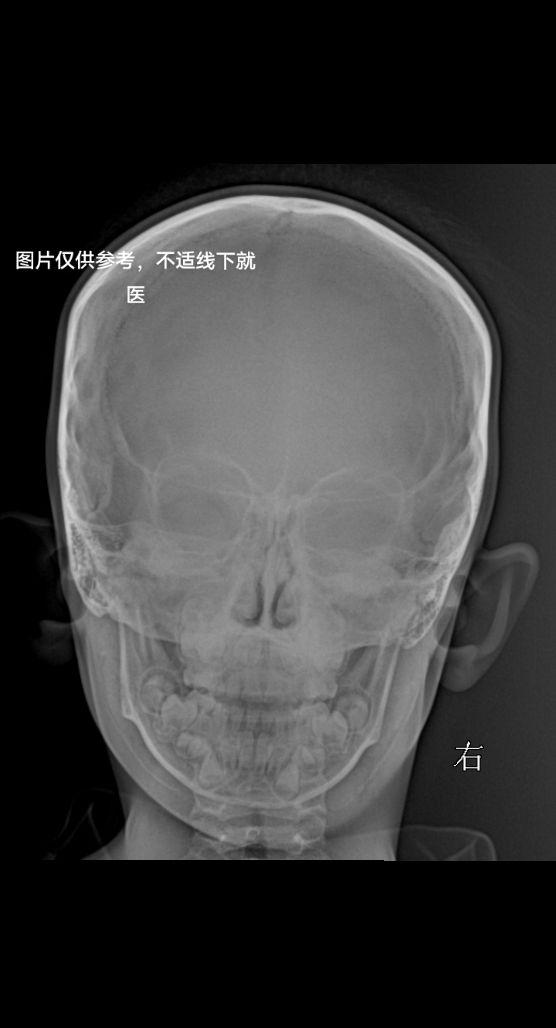

柯瓦氏位,副鼻窦有无问题家人们

2024-06-10 13:07